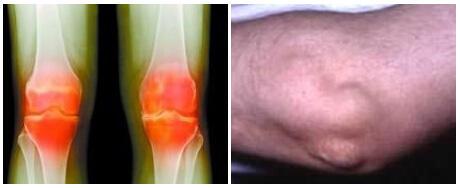

(图:风湿寒性关节痛与风湿性结节炎极易混淆)